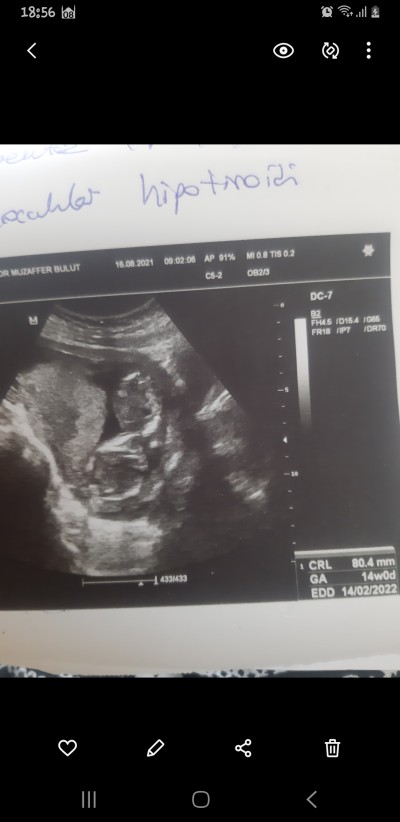

Cinsiyet tahmini

Erkek canım:))

Allahım ilk  önce sağlıklı hayırlı bir erkek evlat  nasip etsin istiyorum zaten  bakalım iki defa  erkek  çocuk rüyanda gördüm ilk defa  hamileligimde rüya  gordum